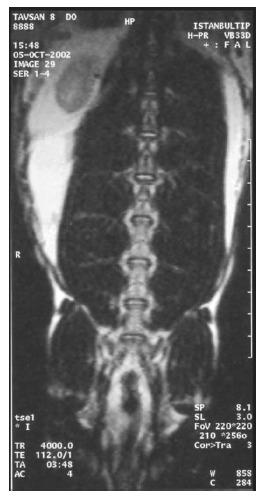

One month later, cultured fibroblasts, which had been taken from the skin, were injected into the disc. The viability and the potential of the injected cells for reproduction were studied histologically and radiologically. Cellular formations and organizations indicating to the histological recovery were observed at the discs to which fibroblasts were transplanted. The histological findings of the discs to which no fibroblasts were transplanted, did not show any histological recovery. Radiologically, no finding of the improvement was found in both groups. The fibroblasts injected to the degenerated discs are viable.

1个月后,将取自皮肤的培养成纤维细胞注入椎间盘。从组织学和放射学方面研究注入细胞的活力及其繁殖潜力。在移植了成纤维细胞的椎间盘中观察到了表明组织学恢复的细胞形成和组织情况。未移植成纤维细胞的椎间盘的组织学检查结果未显示任何组织学恢复情况。放射学方面,两组均未发现改善迹象。注入退变椎间盘中的成纤维细胞是有活力的。